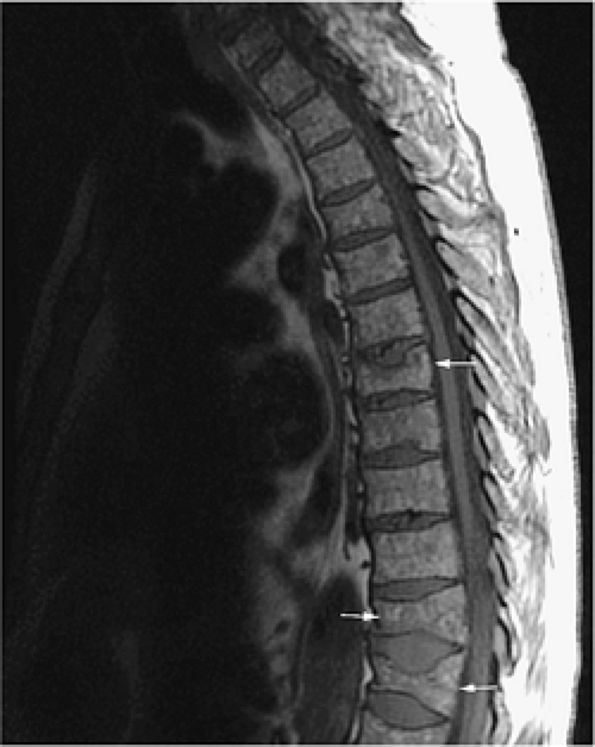

![]() |

FIGURE 13.11 ● Diffuse low-signal-intensity leukemic infiltration of marrow occurs in acute lymphocytic leukemia, as seen on T1-weighted sagittal images of the cervical (A) and thoracolumbar (B) spine.